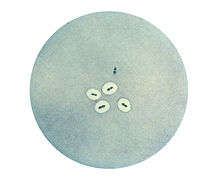

Photomicrograph of Streptococcus pneumoniae bacteria revealing capsular swelling using the Neufeld quellung test. Notice the two streptococci at the top of the photo that appear to have no capsule.

The quellung reaction, also called the Neufeld reaction, is a biochemical reaction in which antibodies bind to the bacterial capsule of Streptococcus pneumoniae, Klebsiella pneumoniae, Neisseria meningitidis, Bacillus anthracis, Haemophilus influenzae,[1] Escherichia coli, and Salmonella. The antibody reaction allows these species to be visualized under a microscope. If the reaction is positive, the capsule becomes opaque and appears to enlarge.

Quellung is the German word for "swelling" and describes the microscopic appearance of pneumococcal or other bacterial capsules after their polysaccharide antigen has combined with a specific antibody. The antibody usually comes from a bit of serum taken from an immunized laboratory animal. As a result of this combination, and precipitation of the large, complex molecule formed, the capsule appears to swell, because of increased surface tension, and its outlines become clearly demarcated.